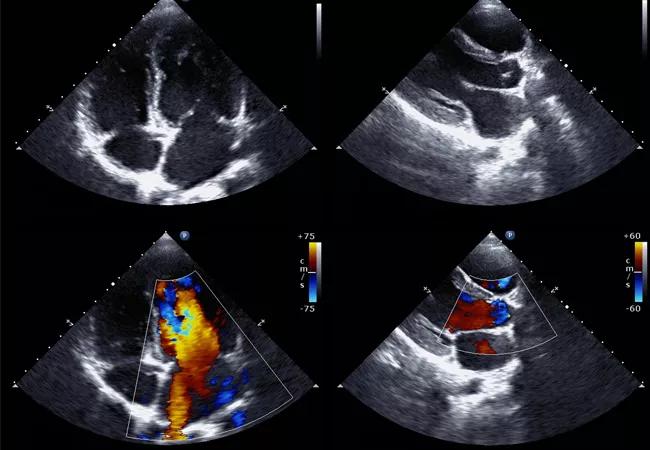

Some echocardiographic features that suggest PAH include a dilated right atrium or ventricle, flattening of the interventricular septum, notching of the right ventricular outflow tract flow and dilation of the main pulmonary artery.

However, echocardiography provides only an indirect measure of systolic PA pressure. Only a right heart catheterization can provide direct evidence of PAH through accurate pressure measurements. Studies comparing measurements during right heart cath with estimated value on echo demonstrate a reasonable degree of agreement between the tests, but a substantial variability. Echo commonly under- and over-estimates systolic PA pressure, with 95 percent limits of agreement ranging from minus 40 mm Hg to plus 40 mm Hg. A difference of plus or minus 10 mm Hg in systolic PA pressure between echocardiography and catheterization was observed in 48 to 51 percent of patients with PAH, particularly in those with higher systolic PA pressure.